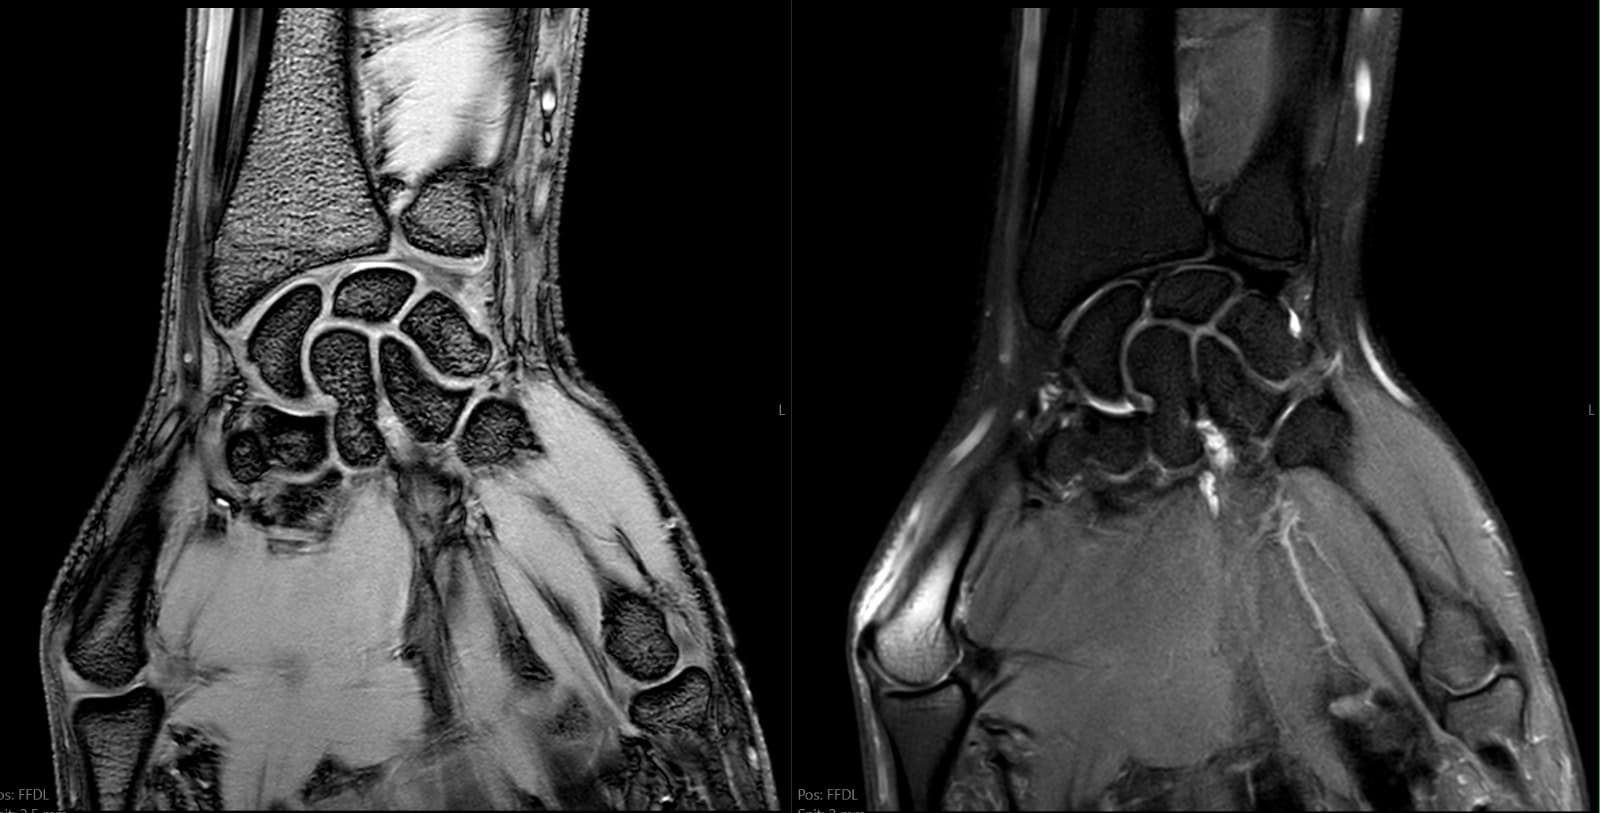

Eksempler fra reelle MSK-kontekster, herunder skulder, knæ, ankel og håndled, hvor strukturerede second opinions ofte giver størst klinisk værdi.

Komplekse skader, smerter, instabilitet, sene/ligament‑patologi, marvabnormiteter og postoperative tilfælde.